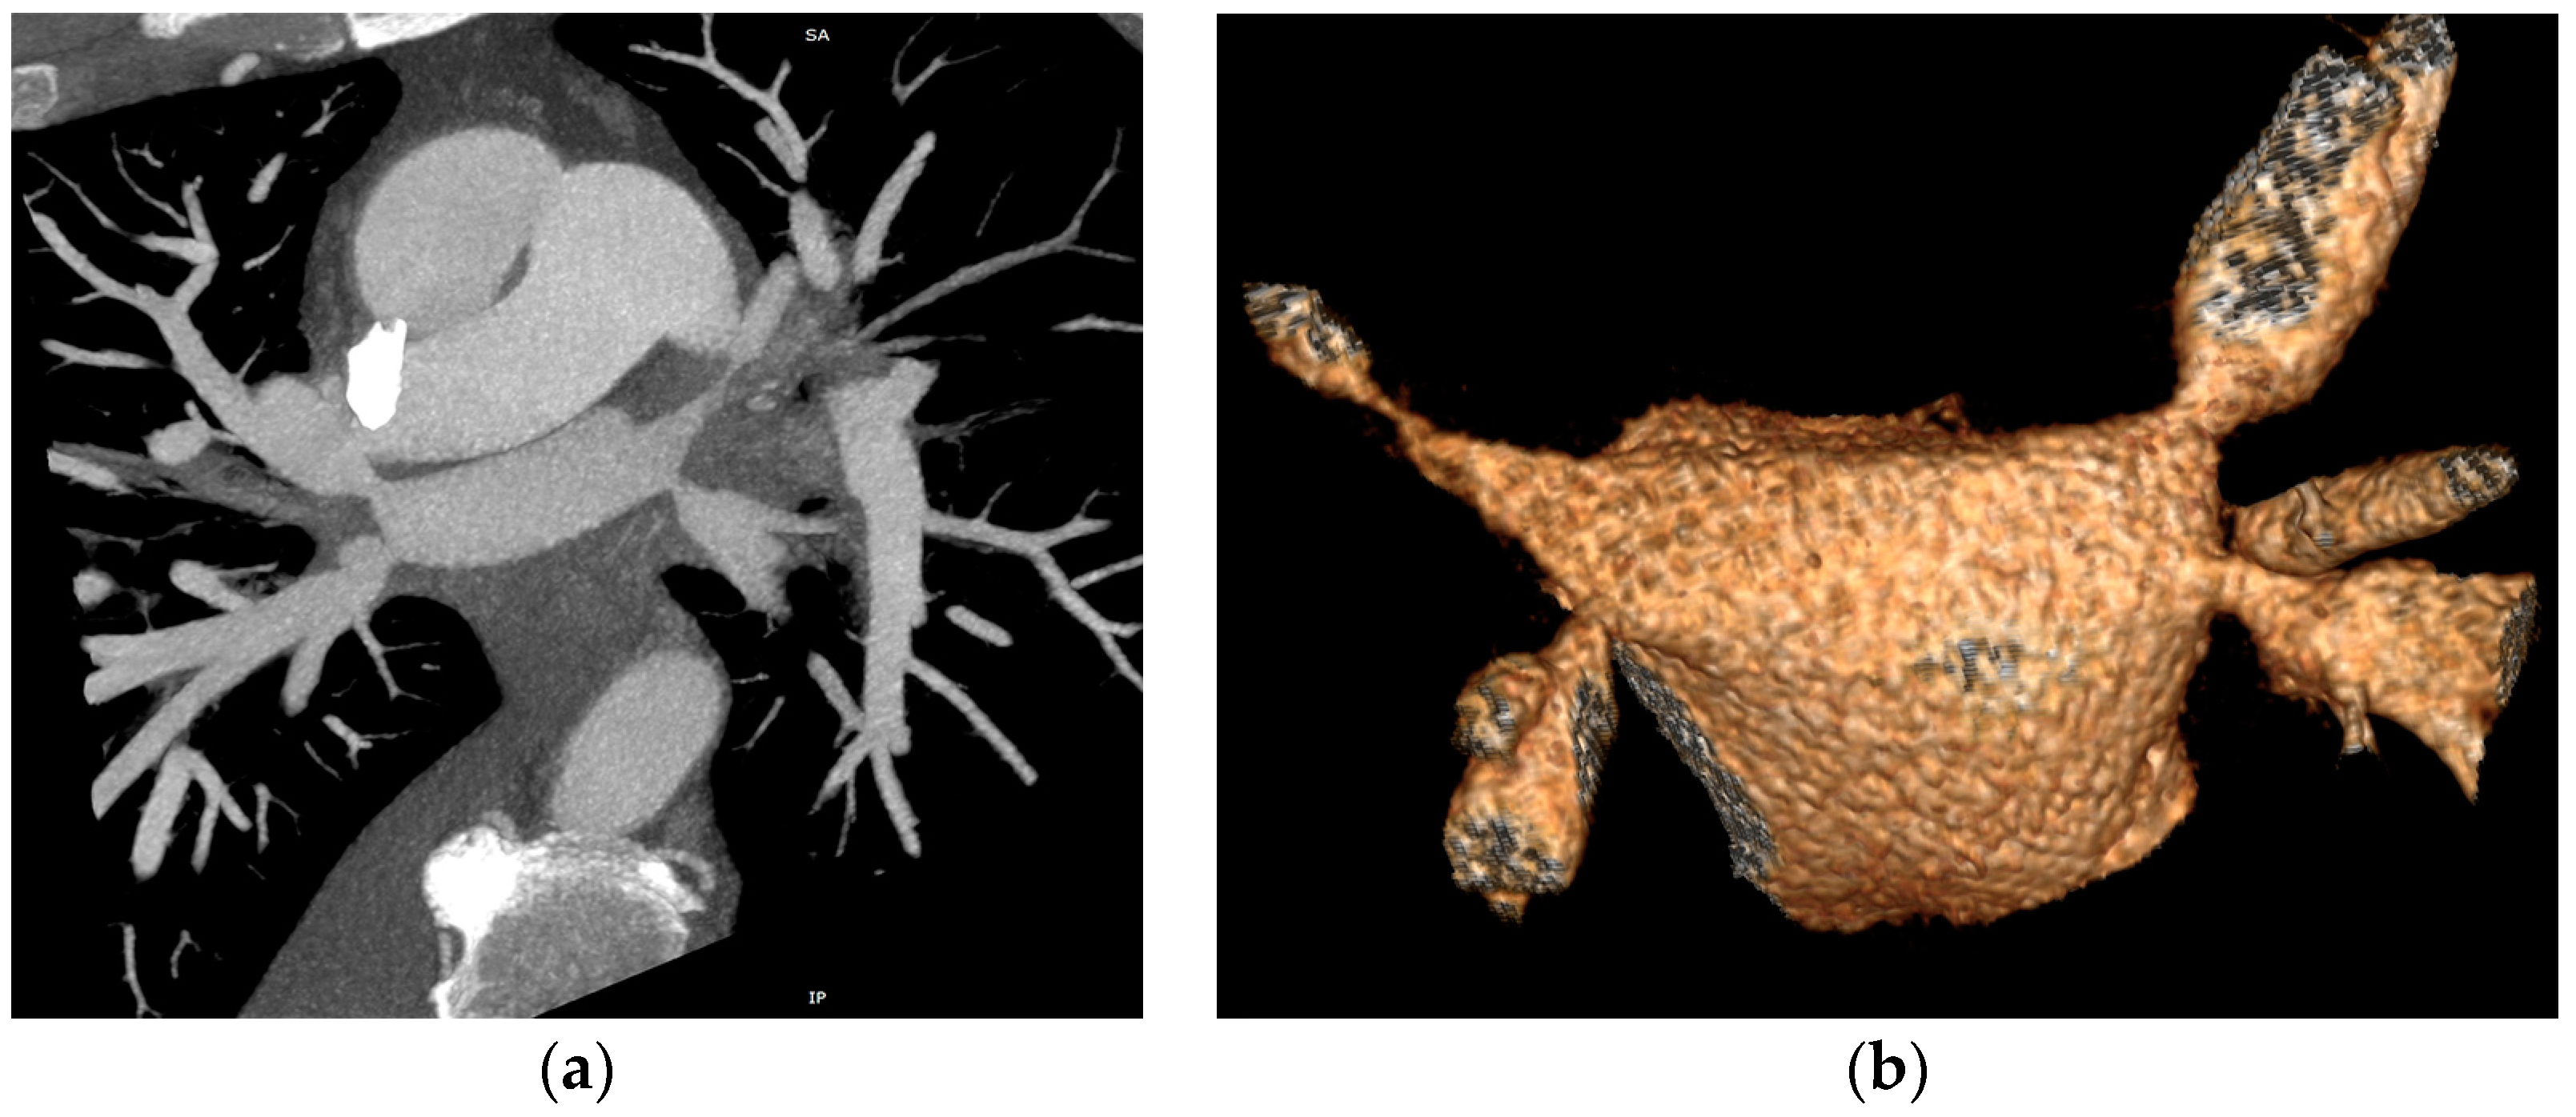

The CT study revealed stenosis of all four pulmonary veins (severe stenosis of the right superior, right inferior and left inferior PVs, near-occlusion of the left superior PV and of the vein draining the apical segment of the right lower lobe) (Figure 2).

Figure 2.

Cardiac CT angiography revealing stenosis of all four pulmonary veins: (a) maximum intensity projection (MIP) reconstruction; (b) volume rendering technique (VRT) reconstruction.

The patient also presented bilateral pleural effusion (40 mm on the right side and 7 mm on the left side) and a soft tissue attenuation obliterating normal mediastinal fat planes and encasing both the PVs and the esophagus posterior to the left atrium, an aspect suggesting fibrosing mediastinitis probably caused by the severe inflammation induced by radiofrequency ablation associated thermal injury (Figure 3). As for the parenchymal findings, a global mosaic attenuation was present, especially in the right middle lobe, together with a ground-glass opacity in the apical segment of the left lower lobe. The parenchymal findings were mostly consistent with pulmonary veno-oclusive disease and an area of hemorrhagic infarction.

Figure 3.

Axial CT image of the mediastinum revealing soft tissue attenuation around the esophagus suggestive for fibrosing mediastinitis.